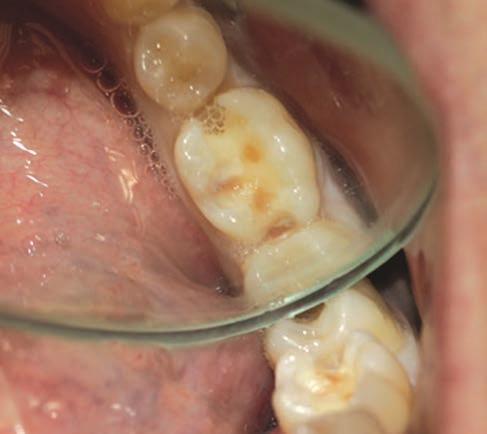

Figure 1: Initial situation: insufficient composite restoration in tooth 36 Figure 2: The cavity after preparation

A female patient presented with an insufficient composite restoration in tooth 36.